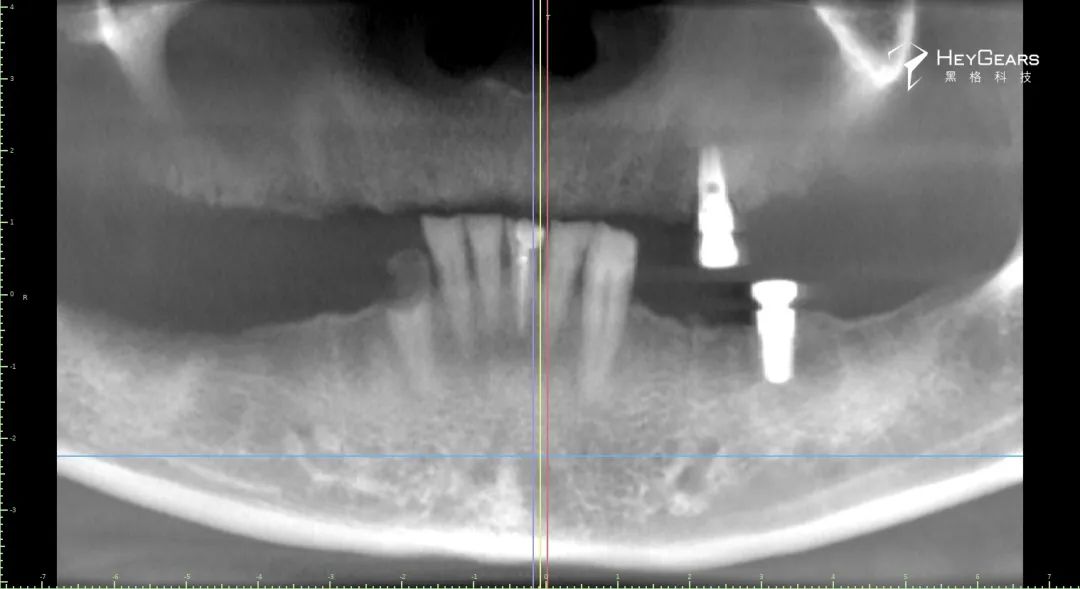

影像学检查:

▲术前CBCT